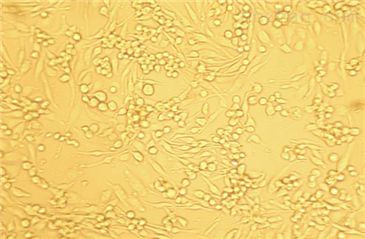

A498

贴壁生长

A498(人肾癌细胞)复苏